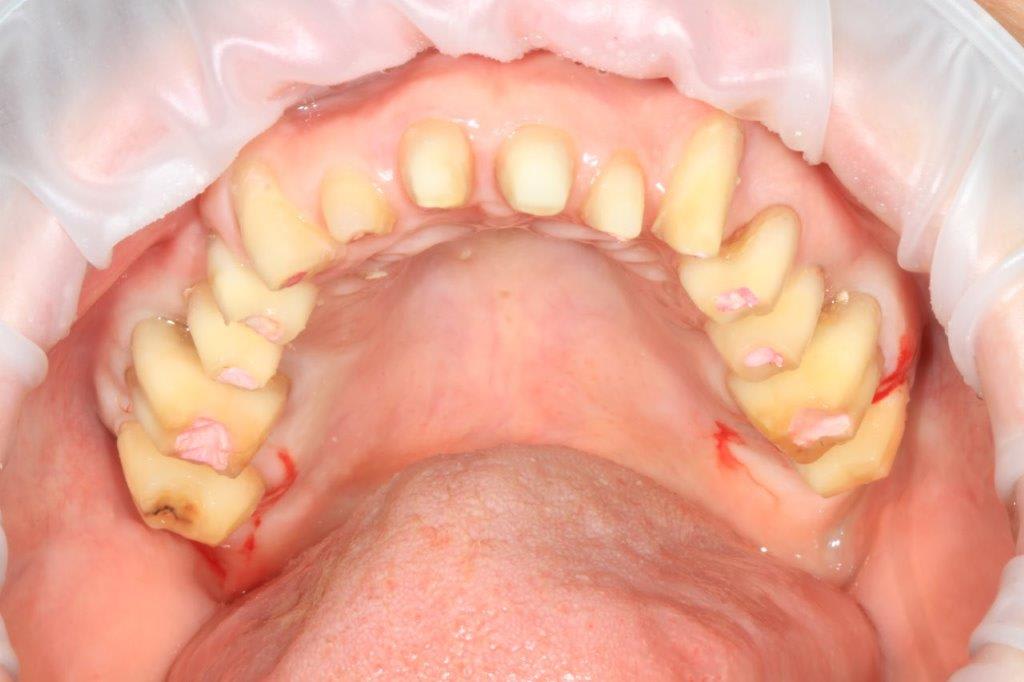

on avance, la patiente est appliquée et commence à gérer le brossage

les différents traitements (endo, détartrages, curetage des poches, bétadine et birodogyl 20 jours, commencent à porter leurs fruits, plus de suintements purulent ...et réduction de la mobilité ...

taille du haut et "bridge" complet provisoire en résine d'après le wax-up...

si tout est "calme" prochaine étape armature métal de contention qui sera recouverte d'Emax press.

mais d'abord quels soins à finir.. ...